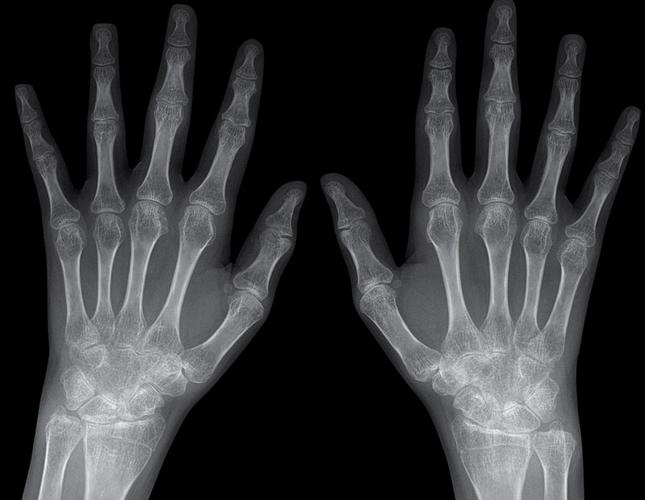

- 影像学检查:

- X光片:早期可能正常,主要用于长期随访,观察骨骼有无破坏。

- 超声:可以发现早期滑膜炎和积液,比X光更敏感。

- MRI:能更清晰地显示关节和软组织的病变,是评估炎症的金标准之一。